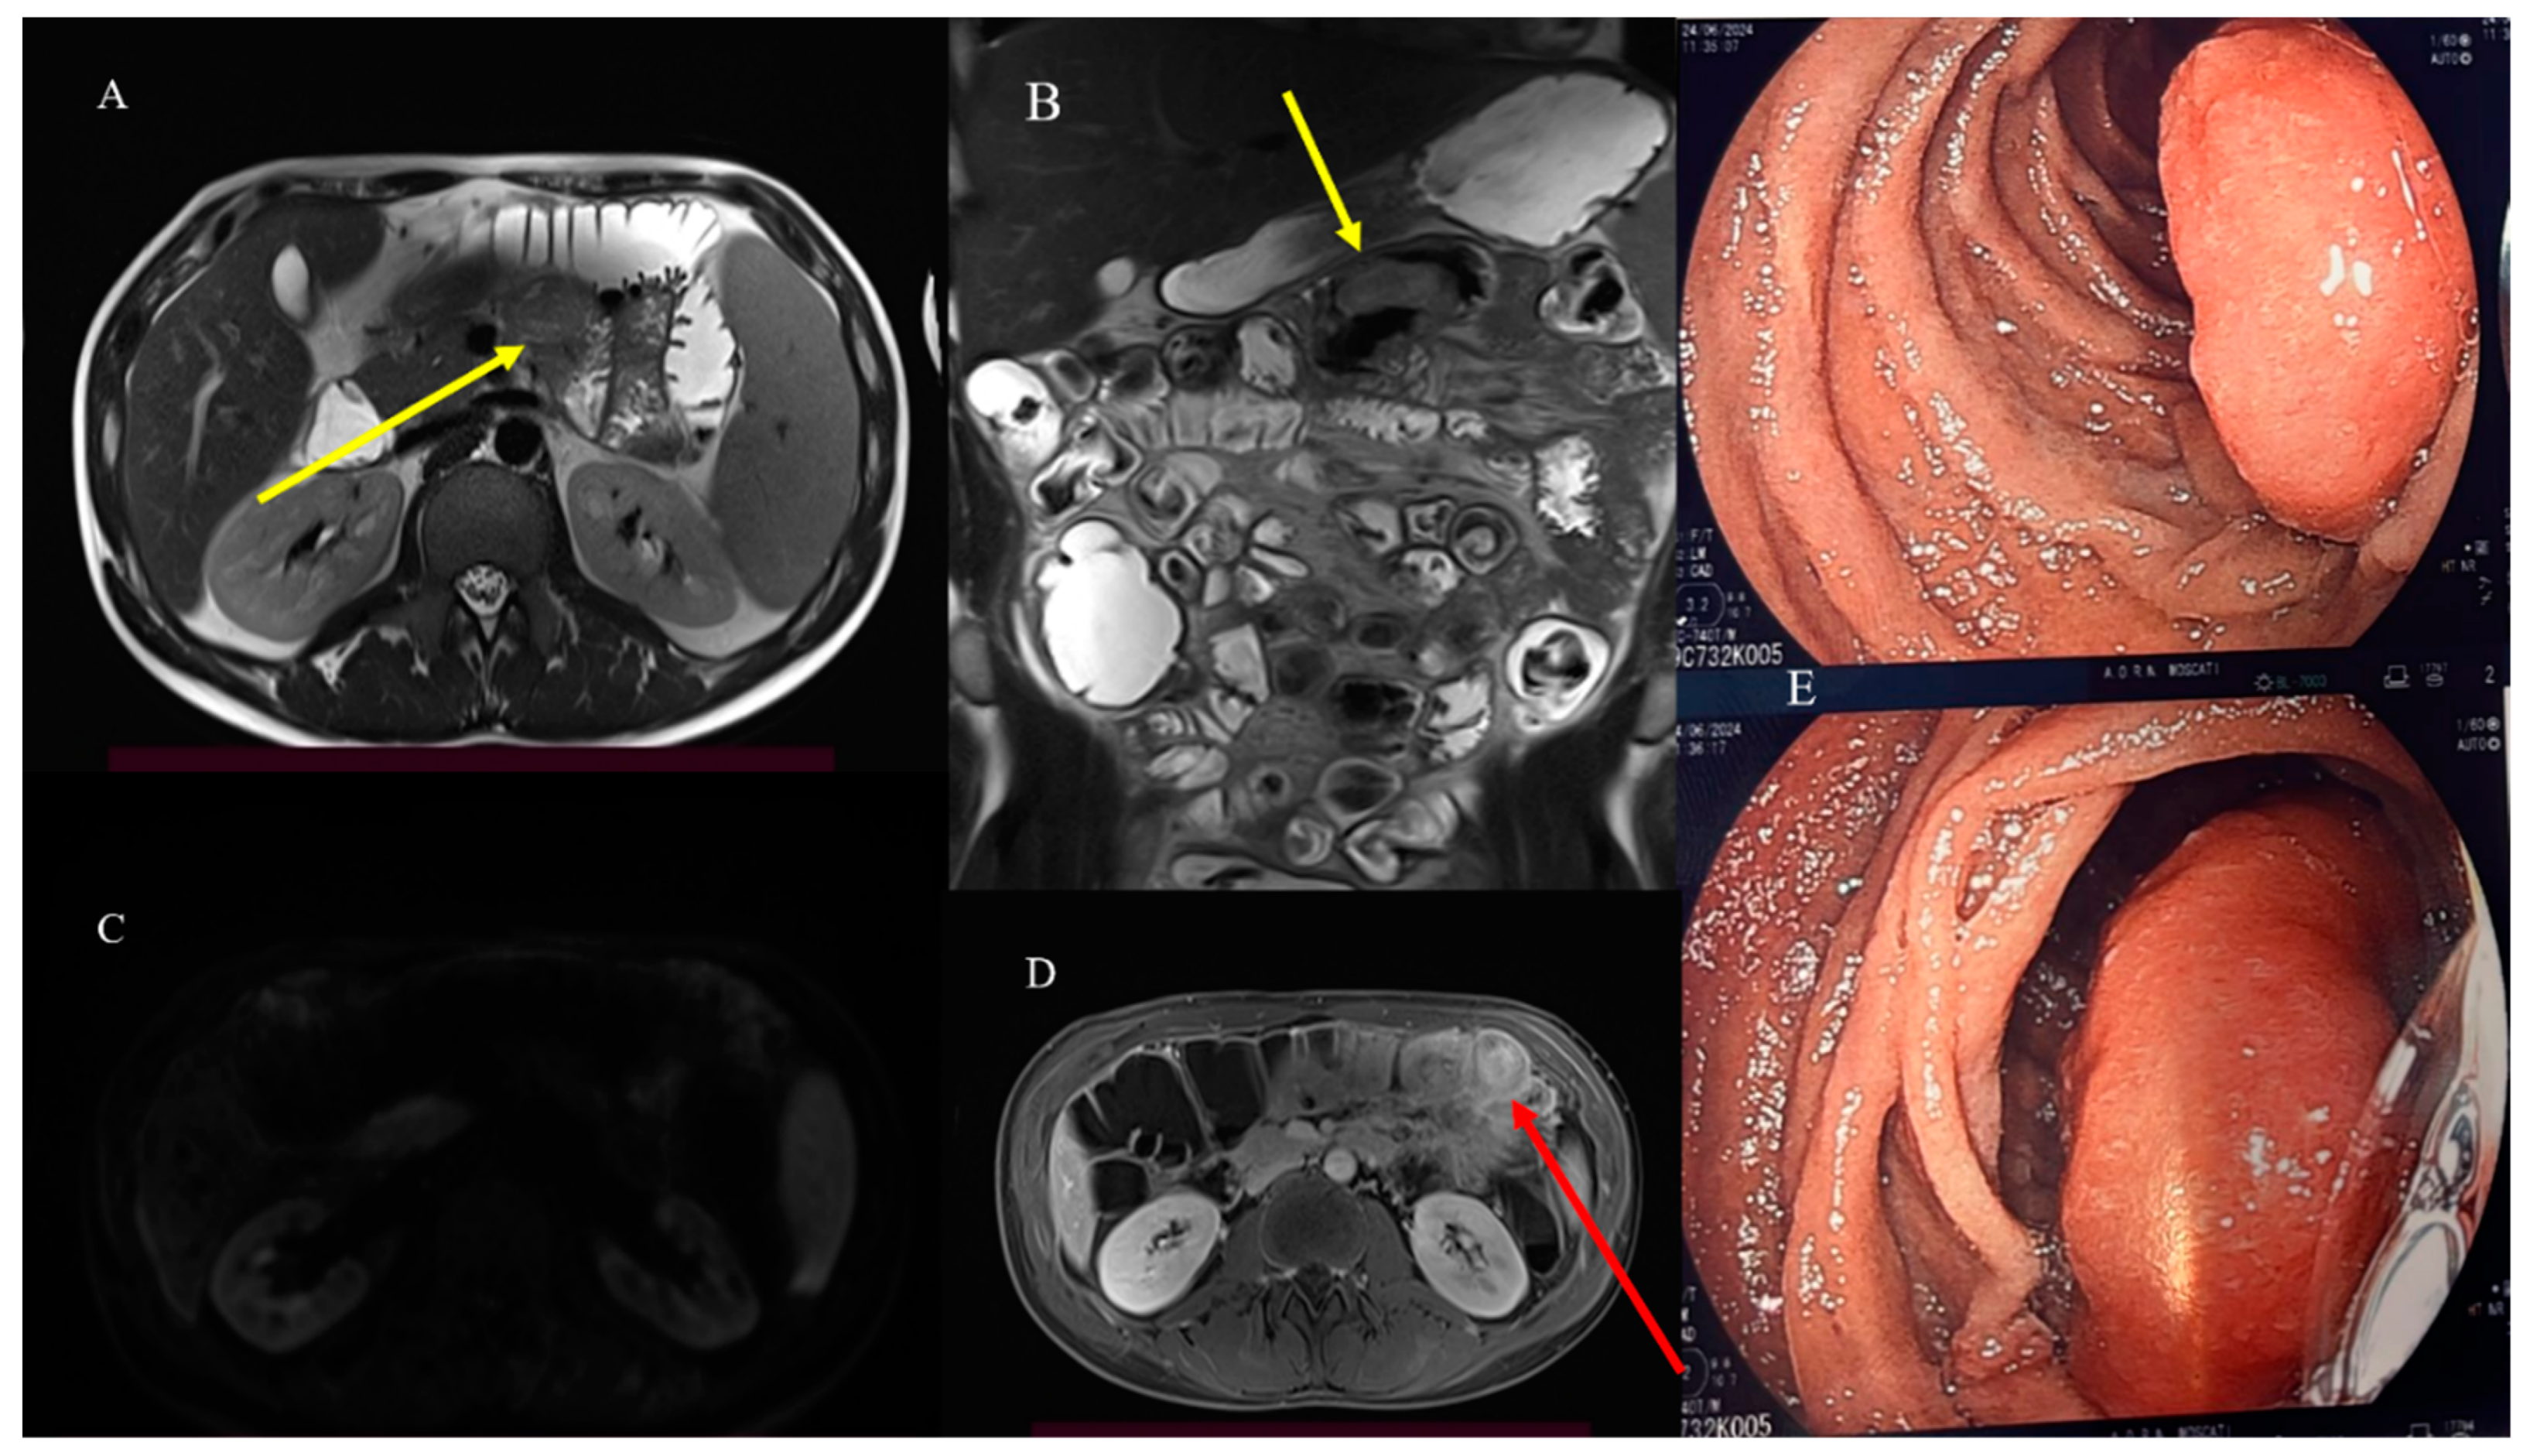

- Masselli, G.; Casciani, E.; Polettini, E.; Laghi, F.; Gualdi, G. Magnetic resonance imaging of small bowel neoplasms. Cancer Imaging 2013, 13, 92–99. [Google Scholar] [CrossRef] [PubMed]

- Faggian, A.; Fracella, M.R.; D’alesio, G.; Alabiso, M.E.; Berritto, D.; Feragalli, B.; Miele, V.; Iasiello, F.; Grassi, R. Small-Bowel Neoplasms: Role of MRI Enteroclysis. Gastroenterol. Res. Pract. 2016, 2016, 9686815. [Google Scholar] [CrossRef]

- Boone, D.; Taylor, S.A. Magnetic Resonance of the Small Bowel: How to Do It. Magn. Reson. Imaging Clin. N. Am. 2019, 28, 17–30. [Google Scholar] [CrossRef] [PubMed]

- Maccioni, F.; Busato, L.; Valenti, A.; Cardaccio, S.; Longhi, A.; Catalano, C. Magnetic resonance imaging of the gastrointestinal tract: Current role, recent advancements and future prospectives. Diagnostics 2023, 13, 2410. [Google Scholar] [CrossRef] [PubMed]

- Pezzella, M.; Brogna, B.; Romano, A.; Torelli, F.; Esposito, G.; Petrillo, M.; Romano, F.; Di Martino, N.; Reginelli, A.; Grassi, R. Detecting a rare composite small bowel lymphoma by Magnetic Resonance Imaging coincidentally: A case report with radiological, surgical and histopathological features. Int. J. Surg. Case Rep. 2018, 46, 50–55. [Google Scholar] [CrossRef]